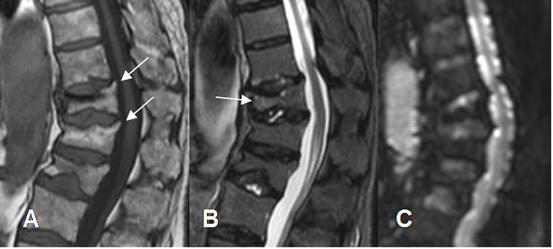

Fig 33. Fracturas por osteoporosis.

A: RM sagital en T1. Pérdida de altura en varios cuerpos vertebrales dorsolumbares. Lo característico, es que conservan su SI y sus bordes son angulados.

B: RM sagital en STIR. La vértebra D11 es algo hiperintensa, indicando evolución aguda por edema y las otras conservan su SI.

D: RM difusión en sagital. SI normal de las vértebras, por fracturas de origen osteoporótico.